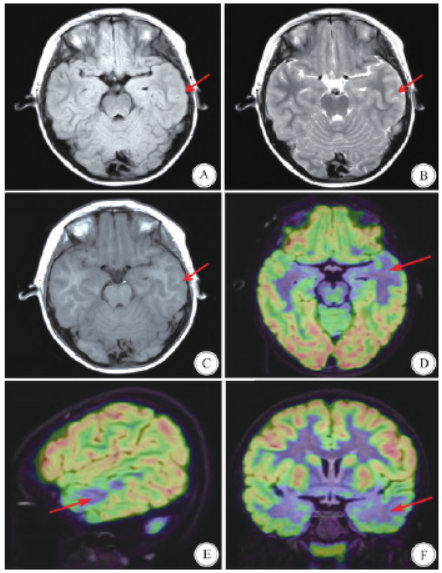

口服液5 mL,2 次/ d,吡仑帕奈片每晚4 mg,服用药物剂量在有效剂量范围内,服药后患者发作控制不佳,智力倒退明显,服用药物后2 h 内嗜睡明显。既往史、个人史、家族史无特殊异常。查体无特殊。头部核磁共振成像

(magnetic resonance imaging,MRI)示左颞叶皮层灰白质交界不清,局灶性皮层发育不良可能性大(图1 A C)。正电子发射计算机断层显像

/ 计算机断层扫描(positron emission tomography/ computed tomography,PET/ CT)示左颞前叶明显低代谢,且左侧颞上回低代谢区向颞后部延伸(图1 D F)。

图1 患儿术前影像学检查。A C:头部轴位MRI 的FLAIR 序列、T2WI 序列、T1WI 序列示左颞皮层灰白质交界不清(红色箭头指示); D F:PET-CT 影像轴位、矢状位、冠状位示左颞前叶明显低代谢,且左侧颞上回低代谢区向颞后部延伸(红色箭头指示)